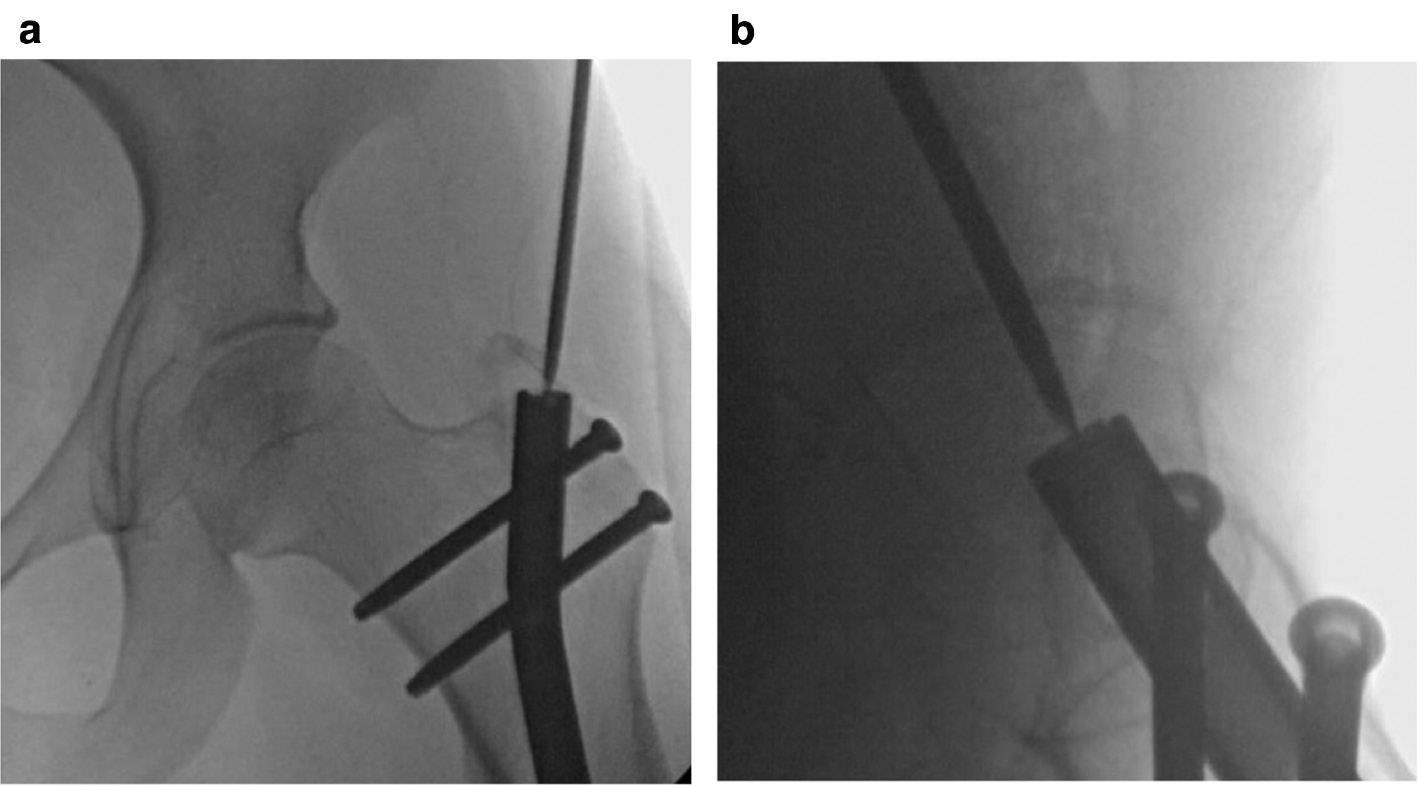

Positioning: Modified Lateral

Alternatively, the patient can be placed in a modified lateral position on a radiolucent table. This allows AP and lateral views to be taken without having to rotate the fluoroscopy machine around the patient. For this position, the patient is secured on the table with a wedge (triangle) pad placed posteriorly at the level of lumbar column and pelvis. This positions the limb at about 45 degrees to the plane of the bed. Rotating the limb 45 degrees internally will allow a lateral view and rotating 45 degrees externally will produce an anteroposterior view (Figure 3a and 3b). The surgeon will need to approach the gluteal region from the direction of the patient’s torso to be in the proper position to remove the nail from the proximal femur. The lower limb that is not operated on can be secured to the table by a strap around the leg and the table. The limb to be operated on should be mobile on the table. The operated extremity can be slightly adducted by positioning it in front of the other leg to improve access to the gluteal region. The limb is prepped from distal to the knee joint and split drapes are used to keep the gluteal region exposed and visible. There should already be a gluteal incision from the nail insertion that can be used as a guide for the extent of the proximal draping exposure required.

Figure 3a (left) and 3b (right). The modified lateral position allows the limb to be rotated from a lateral (3a) to an anteroposterior position (3b) without having to change the orientation of the fluoroscopy machine.